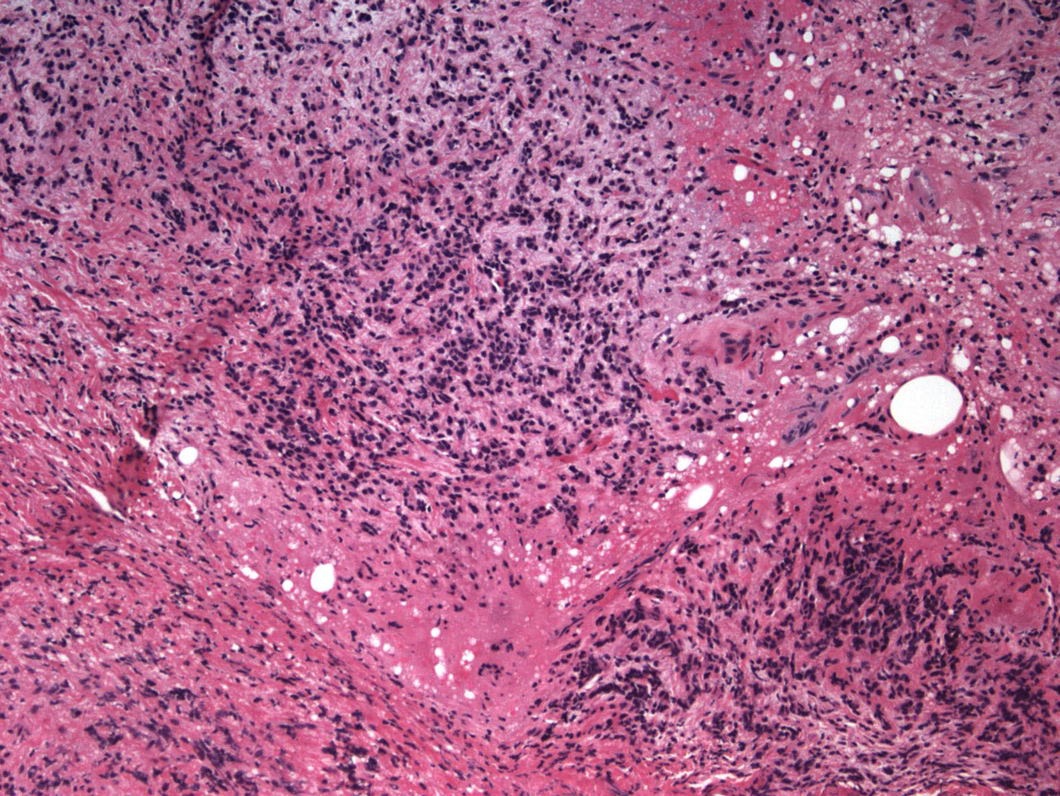

The patient underwent right anterior orbitotomy and biopsy of the intraconal mass. Pathologic examination revealed a dense infiltrate of spindle shaped to round cells with scant cytoplasm and hyperchromatic nuclei. The cells demonstrated an infiltrative growth pattern. Immunohistochemistry testing was positive for estrogen and progesterone receptors. Carcinoembryonic antigen (CEA) demonstrated focal positivity. Pancytokeratin, AE1/3, and Cytokeratin 7 were also positive. CD45 and S100 were negative. These findings were consistent with a poorly differentiated carcinoma with a growth pattern and immunophenotype most consistent with metastatic neoplasm, likely breast or ovary.

Figure 5. H&E Stain of orbital mass biopsy which demonstrates a dense infiltrate of spindle shaped to round cells with scant cytoplasm and hyperchromatic nuclei. The cells demonstrated an infiltrative growth pattern. (click on picture for higher resolution image)

Figure 5.? H&E Stain of orbital mass biopsy which demonstrates a dense infiltrate of spindle shaped to round cells with scant cytoplasm and hyperchromatic nuclei. The cells demonstrated an infiltrative growth pattern